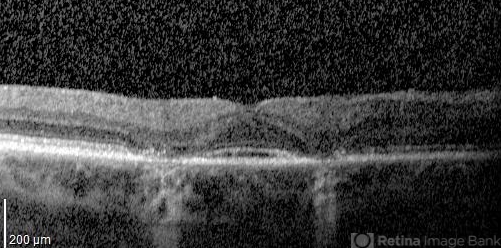

- plaquenil toxicity

- 70-year-old woman with history of plaquenil use for rheumatoid arthritis.